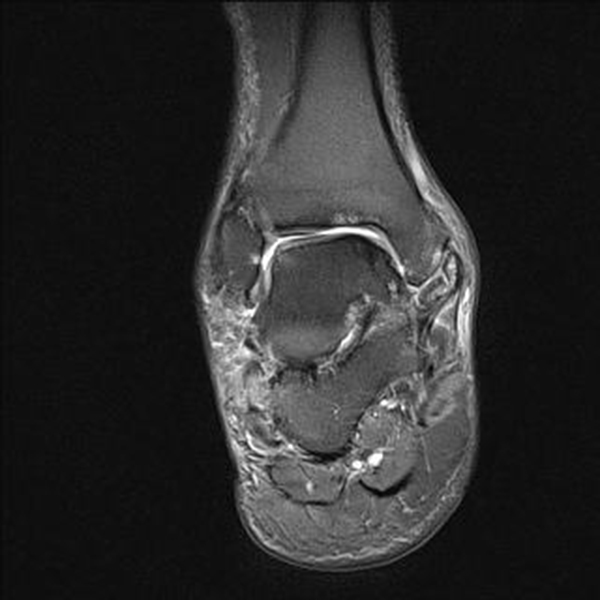

Die Magnetresonanztomographie (MRT) hat gezeigt, dass Knochenprellungen („bone bruises“), Knorpelschäden und andere Weichteil-Verletzungen erkannt werden 13 und mit arthroskopischen Befunden korrelieren 14.

Obwohl die MRT mittlerweile als Goldstandard für die Beurteilung von OCLs gilt sollte bedacht werden, dass aufgrund der hohen Sensitivität der Methode die Signalmuster im Sprunggelenk die Schwere der Knochenverletzung überschätzen können. Zudem wurde die gleiche diagnostische Genauigkeit für CT und MRT festgestellt 15.

Zur Vollansicht und zum Lesen der Bildbeschreibung bitte das Bild anklicken.